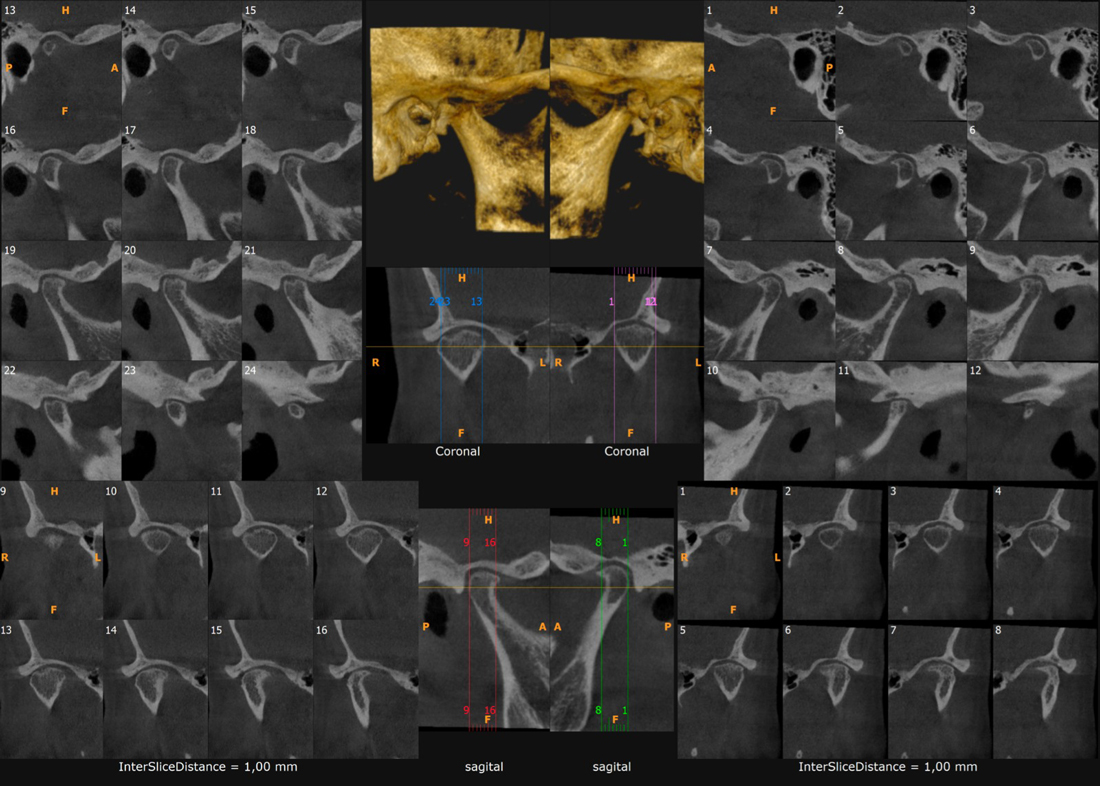

- Se pueden visualizar imágenes de alta calidad en los tres planos del espacio.

- Reconstrucciones tridimensionales a escala real de 1:1.

- Cortes tomográficos a diferentes escalas.

Estudio de Simetría

Nos permite analizar las distintas estructuras craneofaciales y su

relación entre si, para determinar biotipos faciales y predecir líneas de

crecimiento y desarrollo, además de posibles compensaciones